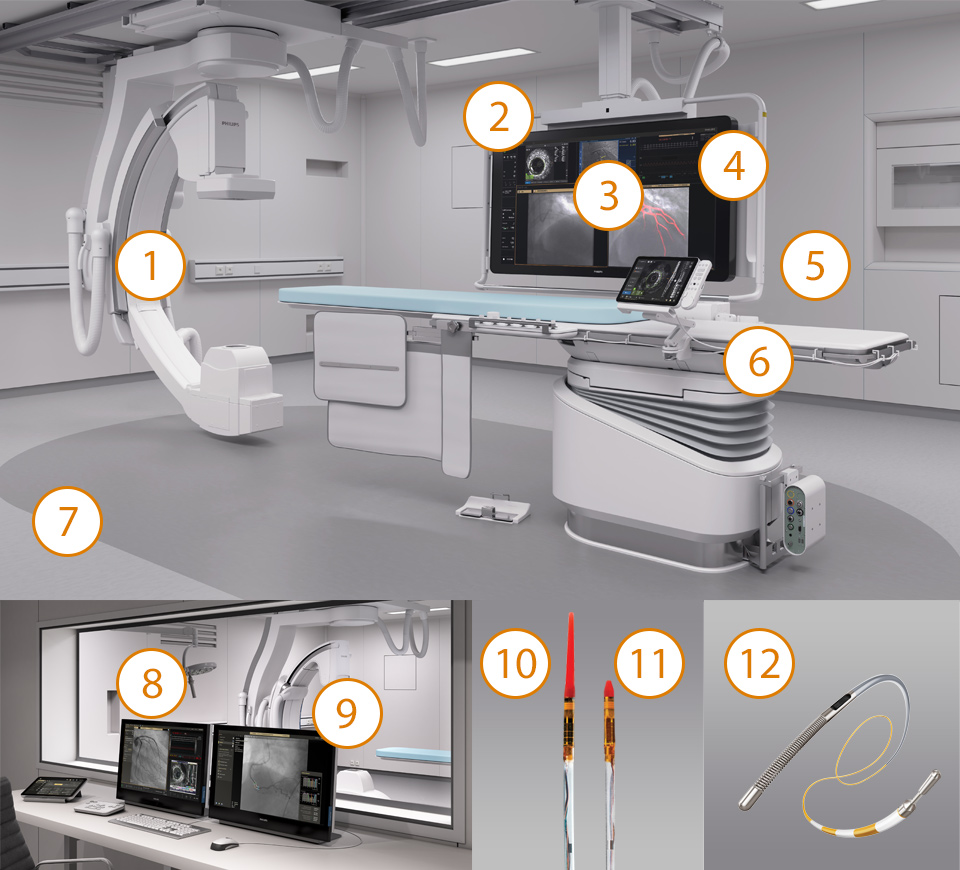

Image-guided therapy, iFR, IVUS and hemodynamic monitoring, as well as cardiac pre-procedure planning and advanced applications, are all connected to the image-guided therapy interface to allow viewing, manipulation, and custom configuration on the monitor from a single controller at table side or from the control room.

Image Guided Therapy System — Azurion

Azurion provides the ability to treat one more patient per day, reducing procedure time by 17%* with optimized workflow options in interventional therapy and clinical software.

Interventional Applications Workstation — IntraSight

Provides more comprehensive clinical insights with seamless integration of iFR/FFR, IVUS and co-registration tools that improve patient health outcomes.You are about to visit a Philips global content page

See clearly, guide confidently — Dynamic Coronary Roadmap

Automatic, real-time navigational guidance designed for procedure efficiency in complex PCI interventions without changing current standard workflow.You are about to visit a Philips global content page

Touch screen module pro

Intuitive touch screen control module at table side. Seamlessly control compatible applications at table side in the sterile field with the enhanced touch screen module Pro. Access physiology, IVUS, hemodynamic measurements, interventional tools and all imaging parameters – to work quickly and decisively. Controlling these applications in the exam room can save time, reduce equipment clutter, and help you focus on the patient.You are about to visit a Philips global content page

Interventional Hemodynamic System with IntelliVue X3

Brings advanced hemodynamic measurements to the cath lab. It integrates with the Philips IntelliVue X3 patient monitor to enable continuous patient monitoring before, during, and after the procedure.You are about to visit a Philips global content page

Azurion 7 M12

Experience outstanding interventional cardiac and vascular performance on the Azurion 7 Series with 12'' flat detector. This industry leading image-guided therapy solution supports you in delivering outstanding patient care and increasing your operational efficiency by uniting clinical excellence with workflow innovation. Seamlessly control all relevant applications from a single touch screen at table side, to help make fast, informed decisions in the sterile field.

IntraSight

The IntraSight Interventional Applications Workspace is where imaging, physiology, co-registration* and software all come together to clearly identify coronary and peripheral artery disease, and allow for more optimized treatment plans. IntraSight is built on a new foundational platform designed to meet the evolving needs of your lab today and tomorrow.

Dynamic Coronary Roadmap

Dynamic Coronary Roadmap, a Philips-exclusive technology, creates a motion-compensated, real-time view of coronary arteries. Recent evidence demonstrates that DCR can reduce contrast agent by 28.8% during a PCI procedure. With DCR a highlighted coronary angiogram is superimposed on a live 2D fluoroscopic image, creating a colored roadmap that adjusts automatically, providing continuous visual feedback on positioning of wires and catheters.

Hemo with IntelliVue X3

Improving productivity and outcomes is vital for healthcare facilities to meet the growing demand for cath lab procedures. To further simplify cath lab workflow, Philips introduces the Interventional Hemodynamic system (Hemo system) which brings advanced hemodynamic measurements to the cath lab. Integration with the IntelliVue X3 patient monitor helps to enable confident clinical decision making and gap-free patient medical records, continuously monitoring the patient in the cath lab or extended throughout the hospital.